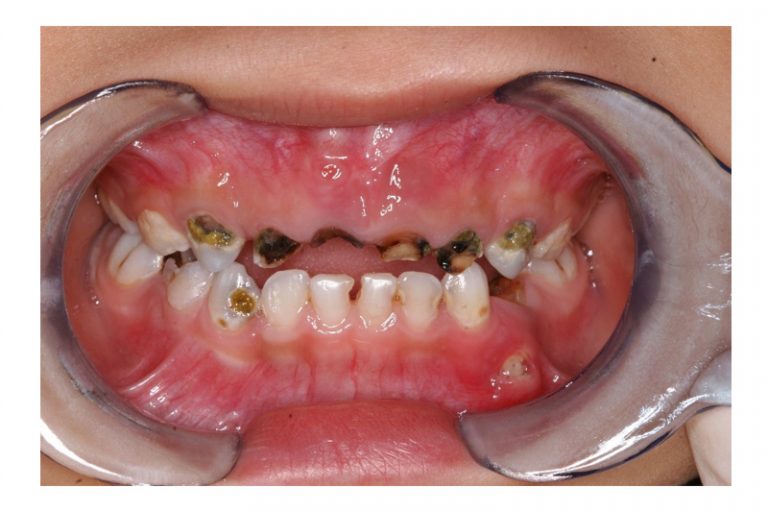

對於有唇顎裂和發育不良等口腔相關問題的特殊兒童,避免吃太硬、太甜的食物。另外,要防止「奶瓶性蛀齒」,即避免幼童睡前喝奶或含奶瓶睡覺的習慣,這樣會令牙齒整晚沾上奶。若家長沒有徹底幫幼童清潔牙齒, 會增其加蛀牙的風險。在正餐和茶點以外,應減少進食次數,並吃一些對牙齒有益的食物例如牛奶、芝士、果仁等,取代無益的食物如蛋糕、糖果、果汁等。這樣能減少細菌分泌酸素,以減低牙齒暴露在酸素的時間,有效預防蛀牙。此外,對於有自閉症、過敏等疾病的特殊兒童,需要避免口腔刺激,如熱飲、酸性食物等,以免造成不適和口腔疾病。

「奶瓶性齲齒」的特徵乃蛀牙主要出現生於上排門牙和第一犬齒,而下排門牙蛀牙較輕微,因為下排門牙靠近唾液腺, 受到舌頭和唾液的保護。